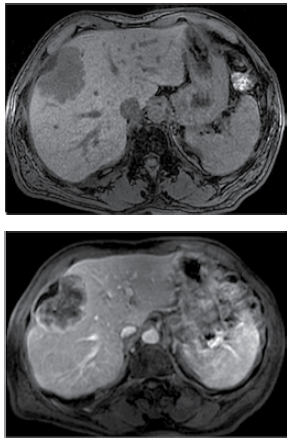

Mulher de 66 anos apresenta quadro de 2 meses de evolução com anorexia, perda de peso, anemia ferropriva e diarreia episódica sanguinolenta. Não há etilismo. A tomografia de abdome realizada é mostrada a seguir.

O exame com maior probabilidade de demonstrar a etiologia do quadro descrito é